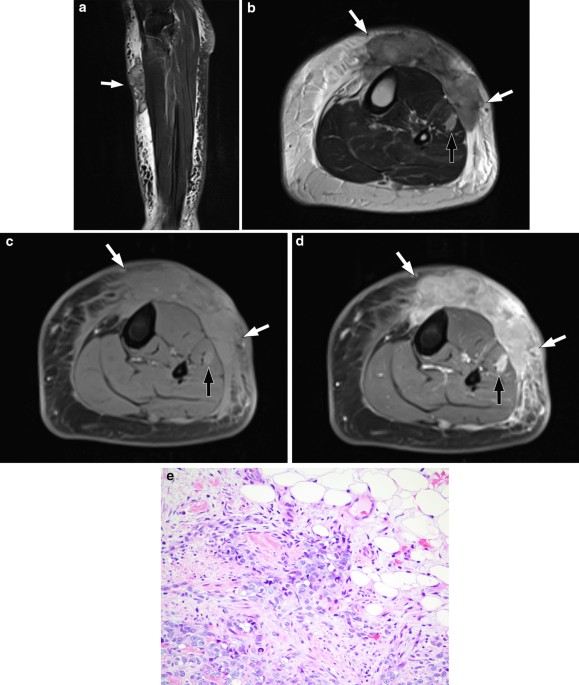

Imaging features of primary sites and metastatic patterns of angiosarcoma, Insights into Imaging